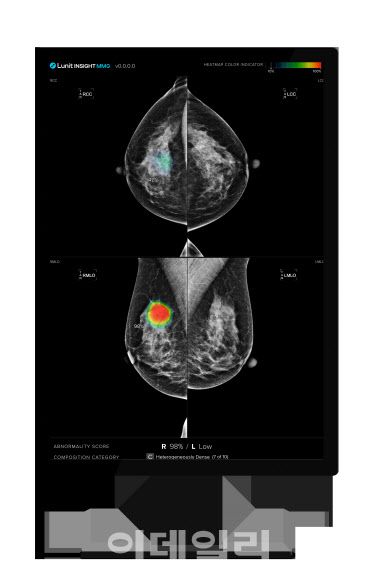

이번 연구들은 각각 미국의학협회의 ‘JAMA Network Open’과 북미영상의학회의 ‘Radiology: Artificial Intelligence’에 게재됐다.노르웨이 공중보건 연구소의 솔베이그 호프빈드 박사 연구팀이 주도한 ‘JAMA Network Open’ 게재 연구는 노르웨이 국가 유방암 검진 프로그램에 참여한 50~69세 여성 11만 6495명의 데이터를 후향적으로 분석했다. 2년 간격으로 3회 실시된 유방촬영 검진 영상을 루닛 인사이트 MMG를 활용해 분석한 결과, AI가 유방암 발생을 최대 6년 전부터 예측할 수 있는 가능성을 확인했다.

AI는 각 유방에 0부터 100까지의 점수를 부여하는데, 점수가 높을수록 유방암 가능성이 높음을 의미한다. 연구 결과, 나중에 암이 발견된 유방과 그렇지 않은 반대쪽 유방 사이의 평균 AI 점수 차이가 시간이 지남에 따라 증가했다. 이 차이는 첫 번째 검진에서 평균 21.3점, 두 번째 검진에서 30.7점, 세 번째 검진에서 79.0점으로 크게 증가했다. 반면, 유방암이 발생하지 않은 여성들의 경우 양쪽 유방 사이의 점수 차이가 모든 검진에서 10점 이하로 낮게 유지됐다. 또한, 연구팀은 AI 점수 91.3 이상인 상위 1%를 ‘고위험군’으로 분류했으며, 발견된 암환자 중 4.5%는 4~6년 전, 8.6%는 2~4년 전, 52.9%는 2년 전에 이미 양성의 가능성을 보이는 AI 점수(10점 이상)를 확인했다.

이번 연구 결과는 AI를 통한 유방암 위험도 정량화로 암 고위험군을 조기에 식별하고, 이들에게 집중적인 모니터링이나 추가 검사를 제공하는 등 맞춤형 예방 및 치료 전략을 수립할 수 있음을 시사한다.